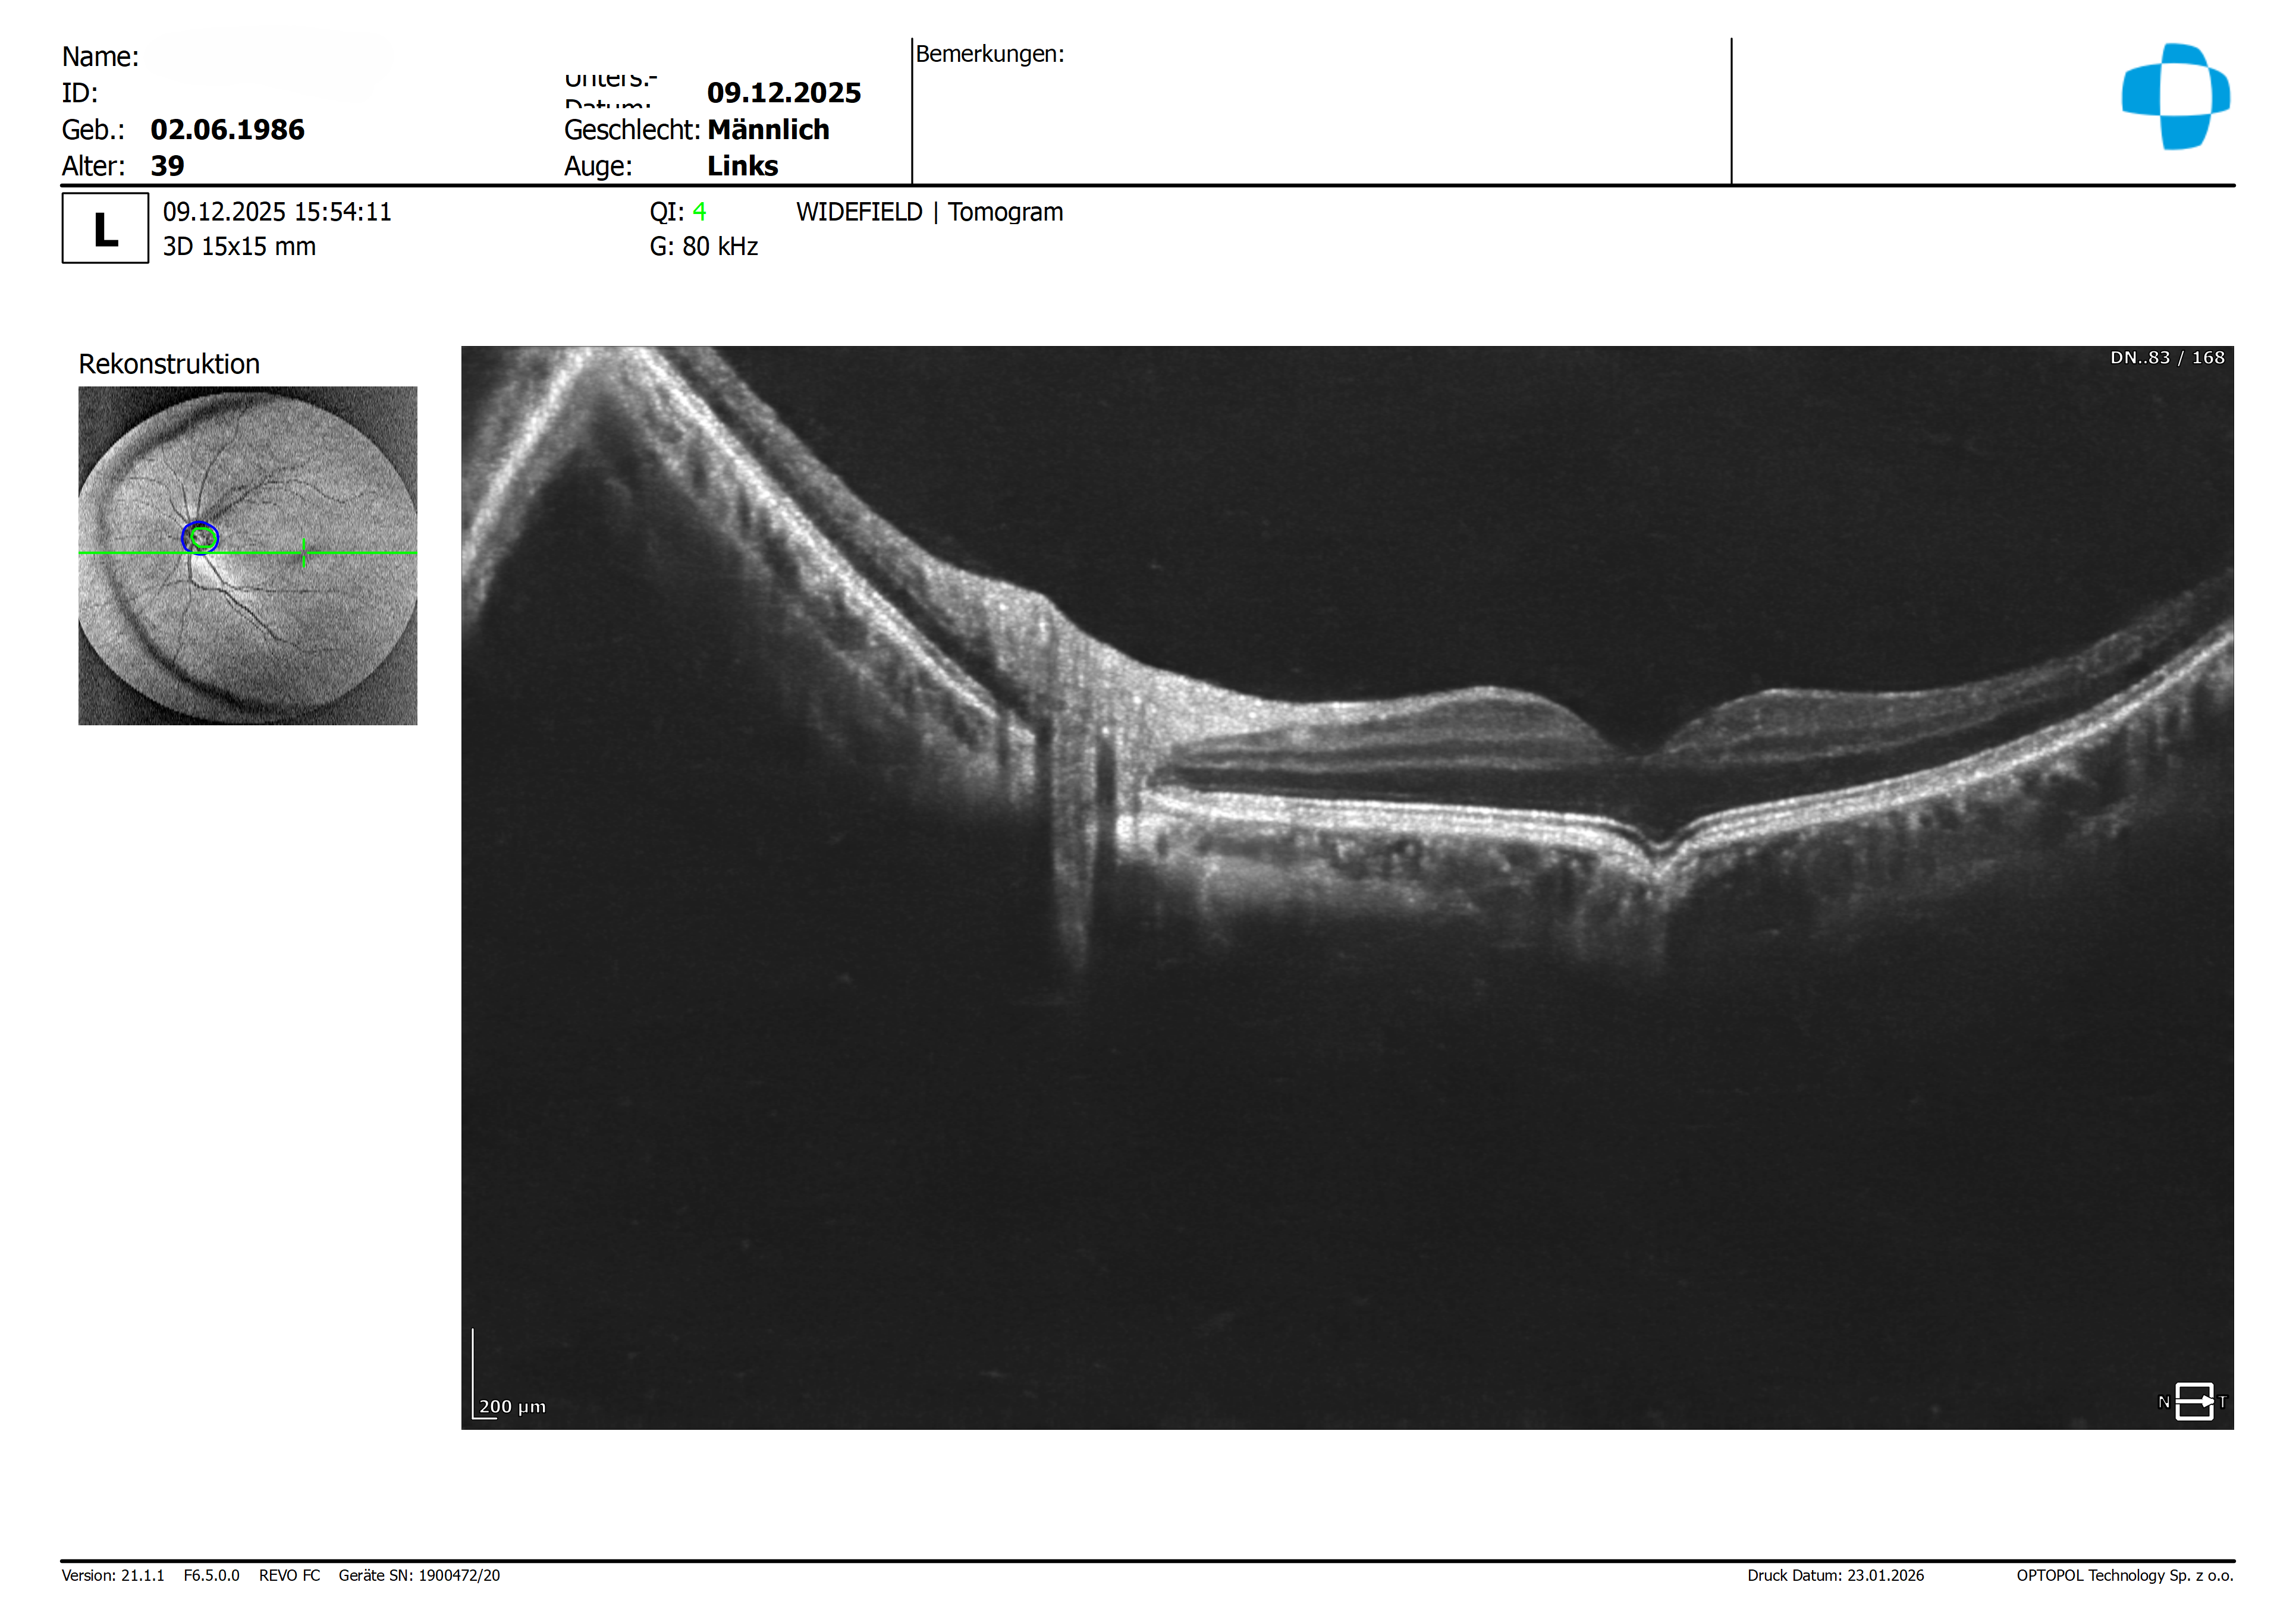

Zur Ergänzung hier noch mal die Widefield Aufnahme links.

Wie bei einer mittleren Myopie üblich haben wir in der Perepherie der NFL eine Dickenreduktion, welche ich jedoch auf Grund der Formänderung des Bulbus als normal einstufen würde.

Auf den vorliegenden Bildern zeigt sich eine atypische Veränderung der Bulbusform im zentralen Foveabereich. Der Bulbus erscheint dort leicht eingezogen, was die beschriebene konkave Konfiguration der äußeren Netzhaut- und Aderhautstrukturen gut erklärt.

Meiner Interpretation nach handelt es sich hierbei weniger um eine pathologische Veränderung als vielmehr um eine anatomische Anomalie, die am ehesten im Sinne eines Mini-Staphyloms zu deuten ist. Beruhigend ist in diesem Zusammenhang, dass sowohl der Netzhautbefund als auch der Visus unauffällig sind.